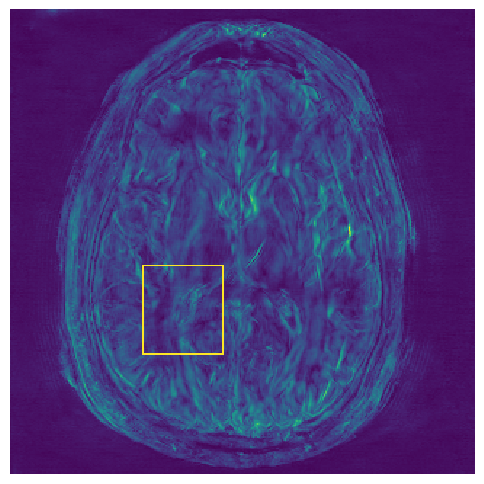

(e) NPB-REC Std.

Figure 3: Reconstructions results. Rows 1 and 3: Examples of comparing the ground truth (GT) fully sampled image to the reconstructed images obtained by the three models (1-3), NPB-REC, baseline, E2E-VarNet trained with Dropout, and the NPB-REC std. map at accelerations R=4𝑅4R=4, R=8𝑅8R=8, respectively. Rows 2 and 4: The corresponding annotated ROIS of Nonspecific white matter lesions.

Fig. 3 presents examples of reconstruction results obtained by (1) our NPB-REC approach, (2) the baseline, and (3) Monte Carlo Dropout, for equispaced masks with two different acceleration rates R=4𝑅4R=4 and R=8𝑅8R=8. The reconstructed images predicted by the three models are smoother than the reference image. This is due to the fact that all the models were trained with SSIM loss, which tends to produce overly smooth reconstructions while preserving the diagnostic content and the anatomical features Sriram et al. (2020a). These images can be enhanced by dithering the image by adding a small amount of random Gaussian noise to produce a more textured reconstruction, as proposed in Sriram et al. (2020b).

Table 1 presents the mean PSNR and SSIM metrics, calculated over the whole inference set, for the three models. Our NPB-REC approach achieved significant improvements over the other methods in terms of PSNR and SSIM (Wilcoxon signed-rank test, pmuch-less-than\ll1e-4, except for SSIM values in line W, R=4𝑅4R=4 where they are roughly the same for NPB-REC and Baseline). The improvement in the reconstruction performance can be noted both quantitatively from the metrics, especially for masks with acceleration rate R=8𝑅8R=8, and qualitatively via the images of annotations, where our results show less smoothness than those obtained by Dropout.